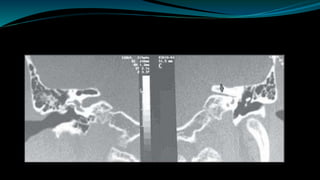

Radiological assessment  Detectanomalies of bony labyrinth  Narrow IAM  Enlarge vestibule aqueduct  Facial nerve dehiscence  Low laying dura  High jugular bulb • Detect labyrinthine ossification • Early fibrotic obstructions. • Identification of cochlear agenesis • Cochlear nerve agenesis • Potency of cochlear duct • Acoustic tumor • CNS abnormalities HRCT MRI